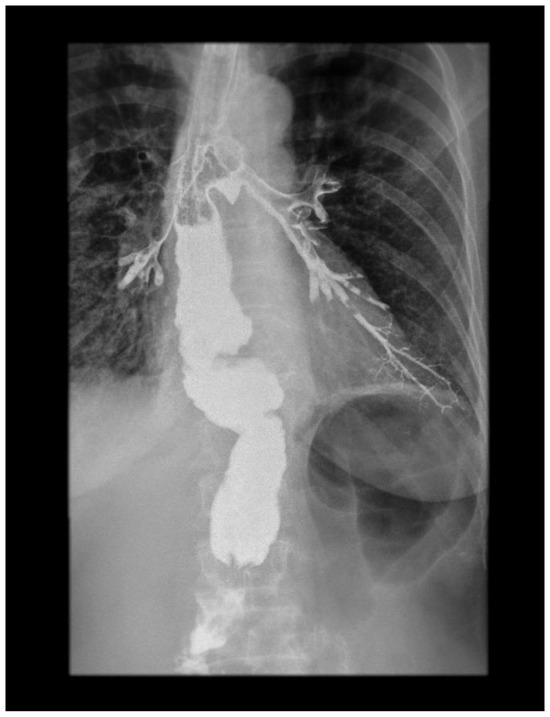

Subsequently, an esophagogram showed the leakage of the contrast medium into the tracheobronchial lumen, demonstrating the presence of a TBF (Figure 2). This was confirmed via MDCT and bronchoscopy. An NG tube was placed for feeding and decompression of the gastric conduit. Antibiotics meropenem (1 g, 8 h) and vancomycin (1 g, 12 h) were administered with the addition of parenteral nutrition.

Figure 2.

Contrast X-ray study showing the gastrobronchial leak. The diagnostic modalities include barium swallow, CT imaging, bronchoscopy, and upper gastrointestinal endoscopy. Identifying TEF can be challenging. Esophagoscopy can often miss small or discrete fistulas, even with fluoroscopy. Contrast radiography is a very useful method in terms of establishing this diagnosis. It is actually the confirmatory test for TEF. The appearance of barium in the lumen of the tracheobronchial tree is a direct sign of the fistulization of these structures within the esophagus. This picture shows a clear esophagobronchial leak, which provoked an irritating cough during the patient’s examination.